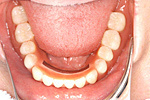

下の顎

① 下の顎・治療前。歯が何もありません。

② 下の顎・インプラントの埋入後

③ 下の顎・セラミッククラウン、ブリッジセット状態

④ 治療後。前から見た状態